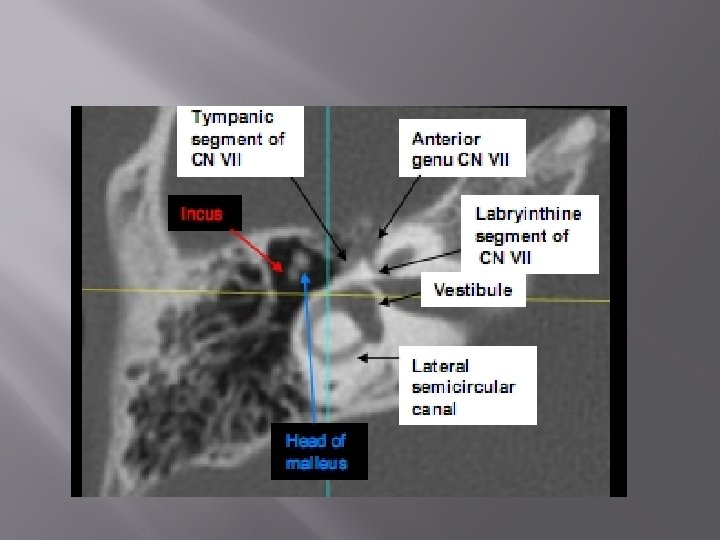

Axial anatomy in CT sections (from inferior to superior)

C=Cochlea, V=Vestibule